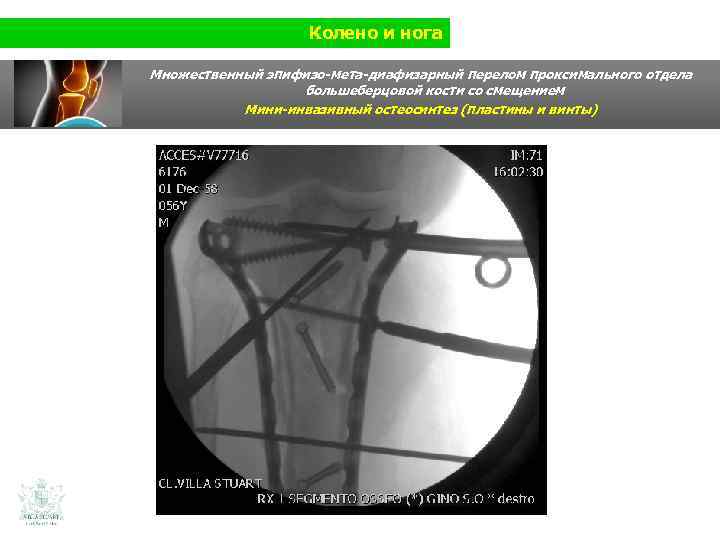

Колено и нога Множественный эпифизо-мета-диафизарный перелом проксимального отдела большеберцовой кости со смещением (Shatzer 6) Мини-инвазивный остеосинтез ( пластины и винты)

Колено и нога Множественный эпифизо-мета-диафизарный перелом проксимального отдела большеберцовой кости со смещением Мини-инвазивный остеосинтез ( пластины и винты)

Колено и нога Множественный эпифизо-мета-диафизарный перелом проксимального отдела большеберцовой кости со смещением Мини-инвазивный остеосинтез (пластины и винты)